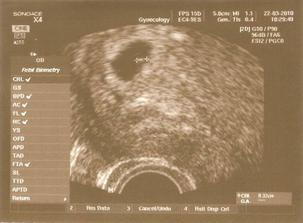

22.3. první návštěva gynekologa, mimi už má srdíčko a prosperuje

12.4. první těhuporadna, 9tt, mimi má necelé 2 cm, vše je v pořádku (ťuk ťuk ťuk), zatím vypadá spíš jako měňavka